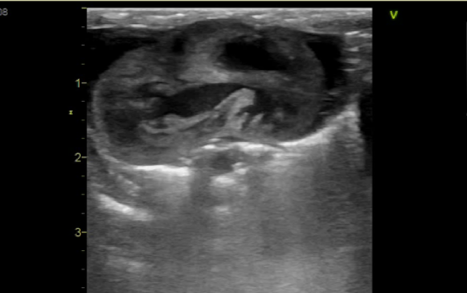

心臓超音波検査は、フトアゴヒゲトカゲの心臓構造、機能、および血流を評価する上で最も価値のある非侵襲的な診断ツールです。

心機能の客観的評価

心臓超音波検査によって、心室の寸法や機能パラメータを計算できます。特に、心室面積変化率(FAC, Fractional Area Change)は、フトアゴヒゲトカゲの心室機能の最も一貫した客観的評価指標として確立されています〔Silverman et al.2016〕。FACの低下は、心筋症や重度の心筋炎に伴う収縮不全を示唆します。例えば、心タンポナーデの症例では、心室のFACが3%から4%に著しく低下したことが報告されています。